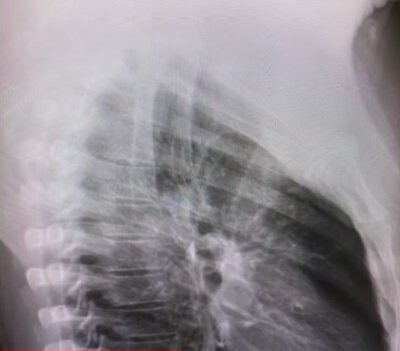

Także dodał to, że później miał wysoką gorączkę około 40 stopni. Amerykańska gwiazda postanowiła podzielić się zdjęciem swoich płuc, który zrobił podczas RTG. W prześwietleniu widzimy nagromadzony płyn.

Lekarze oczekują ode mnie kontroli, ponieważ mam wirusa, i muszę ci powiedzieć – to przerażające, że twoje płuca wznoszą się tam i widzą te rzeczy i mówią: „Cóż, co to jest? Co to takiego tam pali? I mówią ci: „Tak, to wirus” - opowiadał amerykańśki dziennikarz Chris Cuomo.